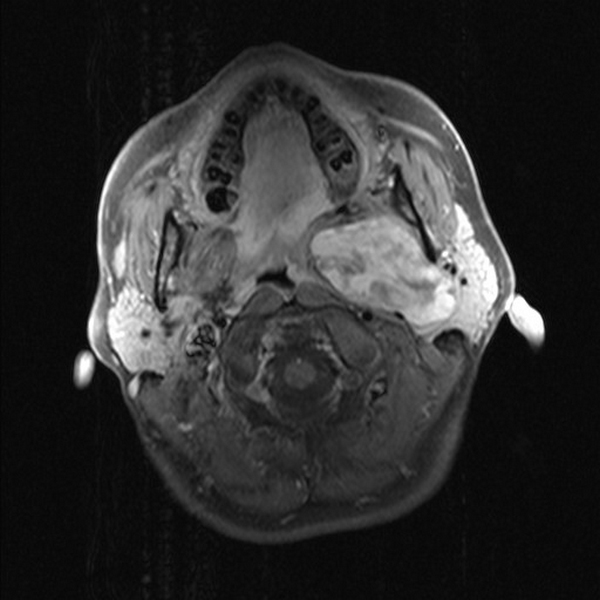

Parapharyngeal pleomorphic adenoma